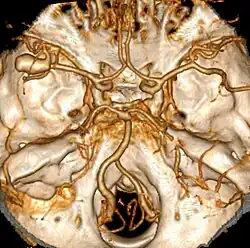

Eine Blutung im sonst gesunden Gehirn entsteht in der Regel an besonderen Schwachstellen des Gefäßsystems. Das sind vor allem zerebrale Aneurysmen. Es handelt sich dabei um sackförmige Aufweitungen arterieller Gefäßwände, die zu einer Wandverdünnung im betroffenen Bereich führen.

Zumeist sind Aneurysmen angeboren. Sie treten dann vorwiegend an Orten erhöhter Belastung durch den Blutstrom auf. Insbesondere Gabelungsstellen von Arterien sind aufgrund von Wirbelbildungen und ähnlichen hämodynamischen Faktoren gefährdet. Betroffen sind dann vor allem Gefäßabschnitte, die durch Arteriosklerose oder entzündliche Arterienkrankheiten verändert sind. Deutlich seltener können Aneurysmen auch im Laufe des Lebens erworben werden. Ein gehäuftes Auftreten findet man bei fibromuskulärer Dysplasie, polyzystischer Nierenerkrankung sowie bei Bindegewebserkrankungen wie dem Marfansyndrom.

Hauptsächlich sind Gefäße betroffen, die den Circulus arteriosus cerebri (Willis) bilden. Dieses Gefäßsystem an der Gehirnbasis verbindet die größten hirnversorgenden Arterien miteinander.

Rupturen (Einrisse) von Aneurysmen der Hirnbasis sind bei 80 % der Erkrankungen Ursache der Subarachnoidalblutung; außerdem kommen Angiome (gutartige Gefäßmissbildungen) und arteriovenöse Fehlbildungen vor. In 5–10 % aller Fälle kann keine Blutungsquelle gefunden werden.[7]

Angiografie

Die zerebrale Angiografie wird als Standardmethode geführt; sie ist ein an Kontrastmittel gebundenes Verfahren der Gefäßdarstellung unter Einsatz von Röntgenstrahlung. Bei hoher Sensitivität muss sie aber in den ersten Stunden durchgeführt werden, da anschließend das Aneurysma als Blutungsquelle verschlossen werden muss, um einen therapeutischen Nutzen zu erlangen. Diese seit langem ausgereifte Methode gilt in ihrer Sonderform, der digitalen Subtraktionsangiografie, den virtuellen Gefäßdarstellungsverfahren von Computertomografie und Kernspin in der diagnostischen Aussagekraft derzeit noch überlegen. Letztere sind jedoch meist schneller erhältlich und für den Patienten weniger belastend.